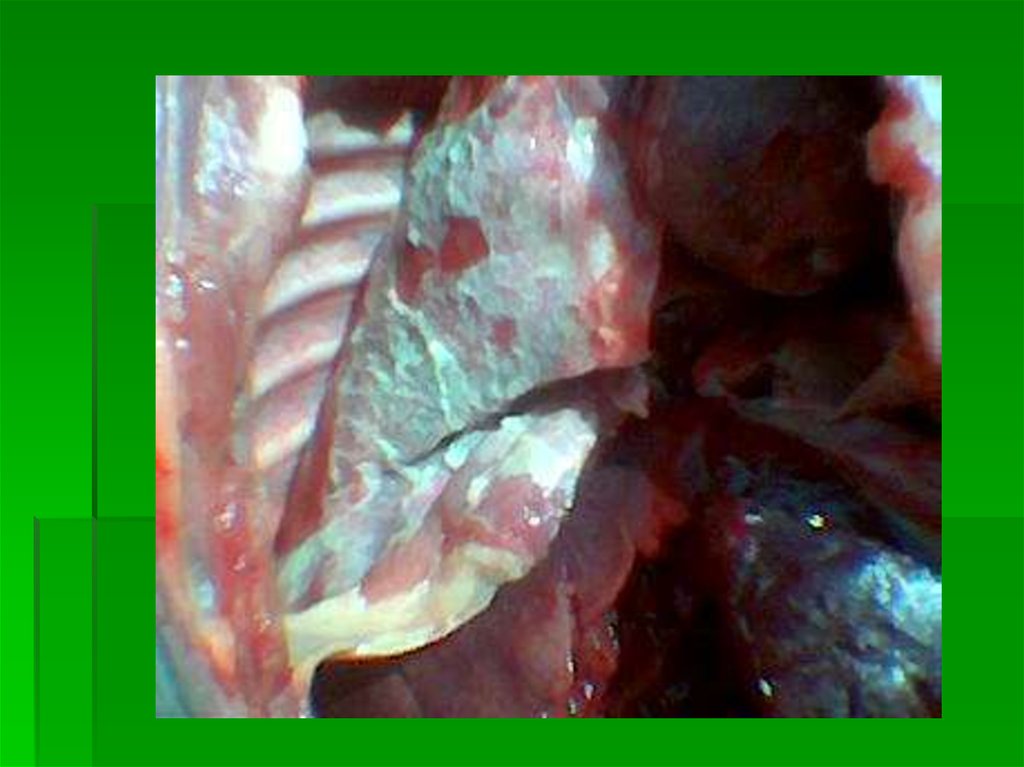

ГЕМОФИЛЕЗ

27. ГЕМОФИЛЕЗ